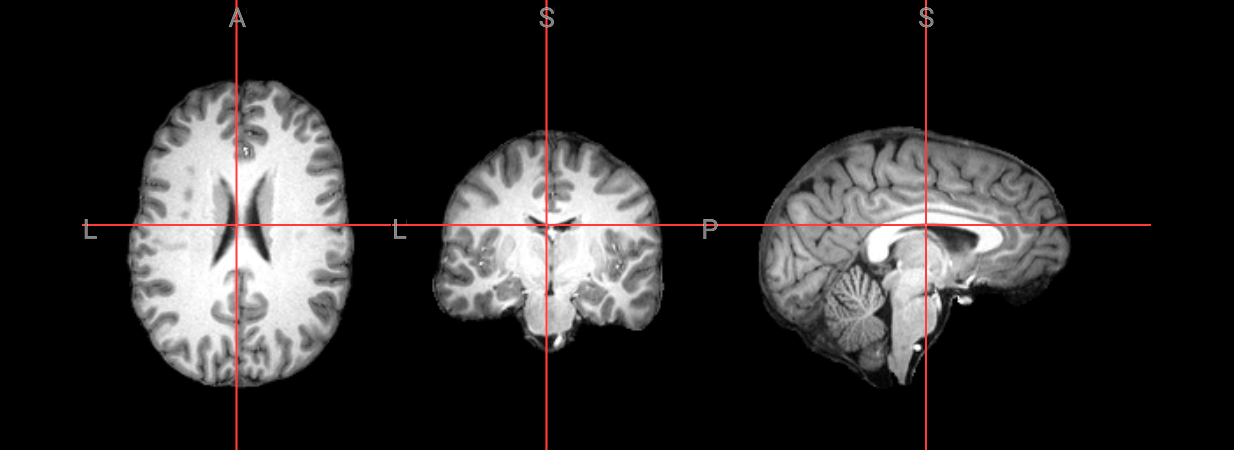

Since fMRI studies focus on brain tissue, our first step is to remove the skull and non-brain areas from the image.